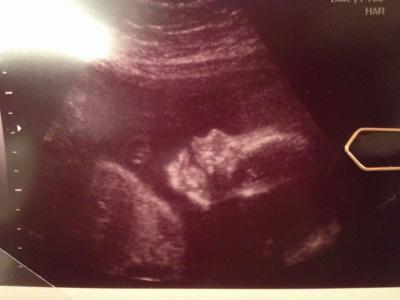

Hallo meine Lieben, ich komm zwar zur zeit nicht so viel zum schreiben aber lese natürlich immer fleißig mit! Heute morgen war es wieder soweit...endlich Termin! Dann die Überraschung...machen wir doch heute gleich mal ctg! Und was soll ich sagen Mädels! Es ist zwar schön den Herzschlag von Krümel zu hören und zu sehen, aber 20 Minuten können echt lang sein...! Danach ab zum Doc und Ultraschall und alles prima! Der kleine Mann hat jetzt schon ca. 1150g und liegt ganz brav mit dem Kopf nach unten! Ab jetzt hab ich immer im 2 Wochen Takt Termin und der nächste ist dann schon am 21.01. Hoffe bei den anderen heute gibt es auch so tolle Nachrichten! P.S. Bin ab heute übrigens in der 29 ssw und das bedeutet 8ter Monat ole!!! Lg Micha

Bild zu FA Bericht - Forum für April - Mamis

Herzlichen Glückwunsch zum 8 Monat. schön das alles in Ordung ist sowas liest man immer gerne. Schönes Bildchen

Hallo meine Liebe! Klasse Bildchen und ich freue mich das bei euch alles in Ordnung ist! 8. Monat olé!!!